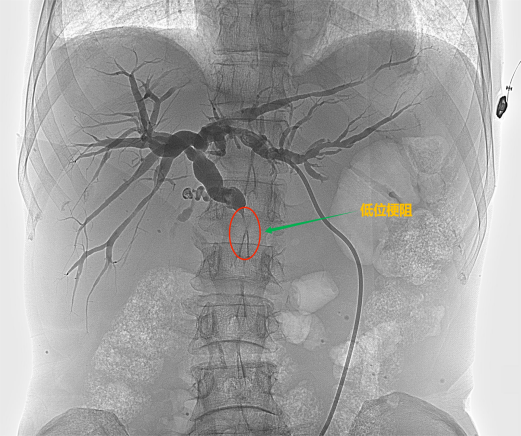

根据梗阻位置的不同可以分为低位胆道梗阻和高位胆道梗阻

低位胆道梗阻

低位胆道梗阻支架置入